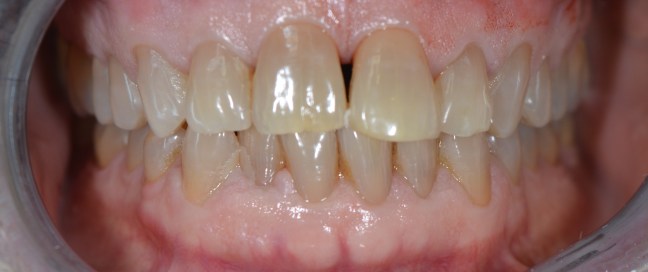

Kozmetikai kezelés: régi tömött, szuvasodott frontfogak szanálása, koronával történő leplezése, megsüllyedt harapás korrekciója.

A választott korona típusa: E-max préskerámia (fémmentes) és cirkon szóló koronák kombinációja.

A választott fogszín A1 .

A protetikai munka elkészülésének ideje: 5 munkanap.